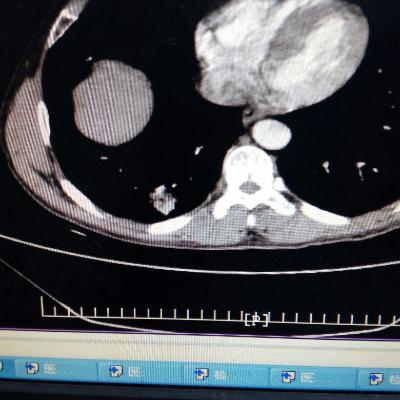

1.胃食管反流病 1.1反流性食管炎LA-B 2.食管裂孔疝 处理:患者诊断明确,行腹腔镜下食管裂孔疝修补术+胃底折叠术。

患者术后一周出院,反酸、烧心、嗳气症状明显缓解,无吞咽不畅等症状。 讨论:对于诊断有食管裂孔疝病人的胃食管反流病,且用药有一定疗效,建议行手术治疗,行腹腔镜下食管裂孔疝修补术,修补了膈裂孔,同时行胃底折叠术,加紧了贲门括约肌压力,共同形成抗“反流瓣”。